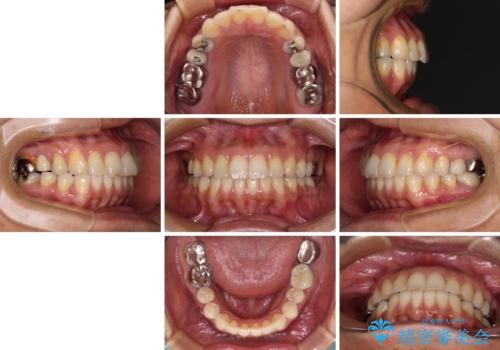

後戻りは軽微であったため、インビザライン・ライトにて歯列を整えました。

矯正治療後には、左下奥歯の症状がないことを確認し、セラミッククラウンにて補綴治療を行うこととしました。

矯正治療後のレントゲン写真では、根尖部に認められた病変(骨の溶けていた像)は消失していることが分かりました。